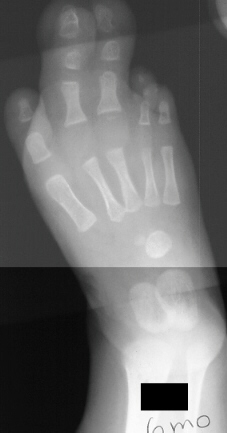

At age 12 months a girl presents severe overgrowth of the foot. She

was the product of a normal pregnancy and delivery and is otherwise completely

healthy. The parents main complaint is that she can not be fitted with

shoes. She had an amputation (image 1 & 2) of the 2nd and 3rd toes

at the level of the mid diaphysis proximal phalanx and extensor tendon

release of the 2nd and 3rd toes with excision of abnormal fibrofatty tissue